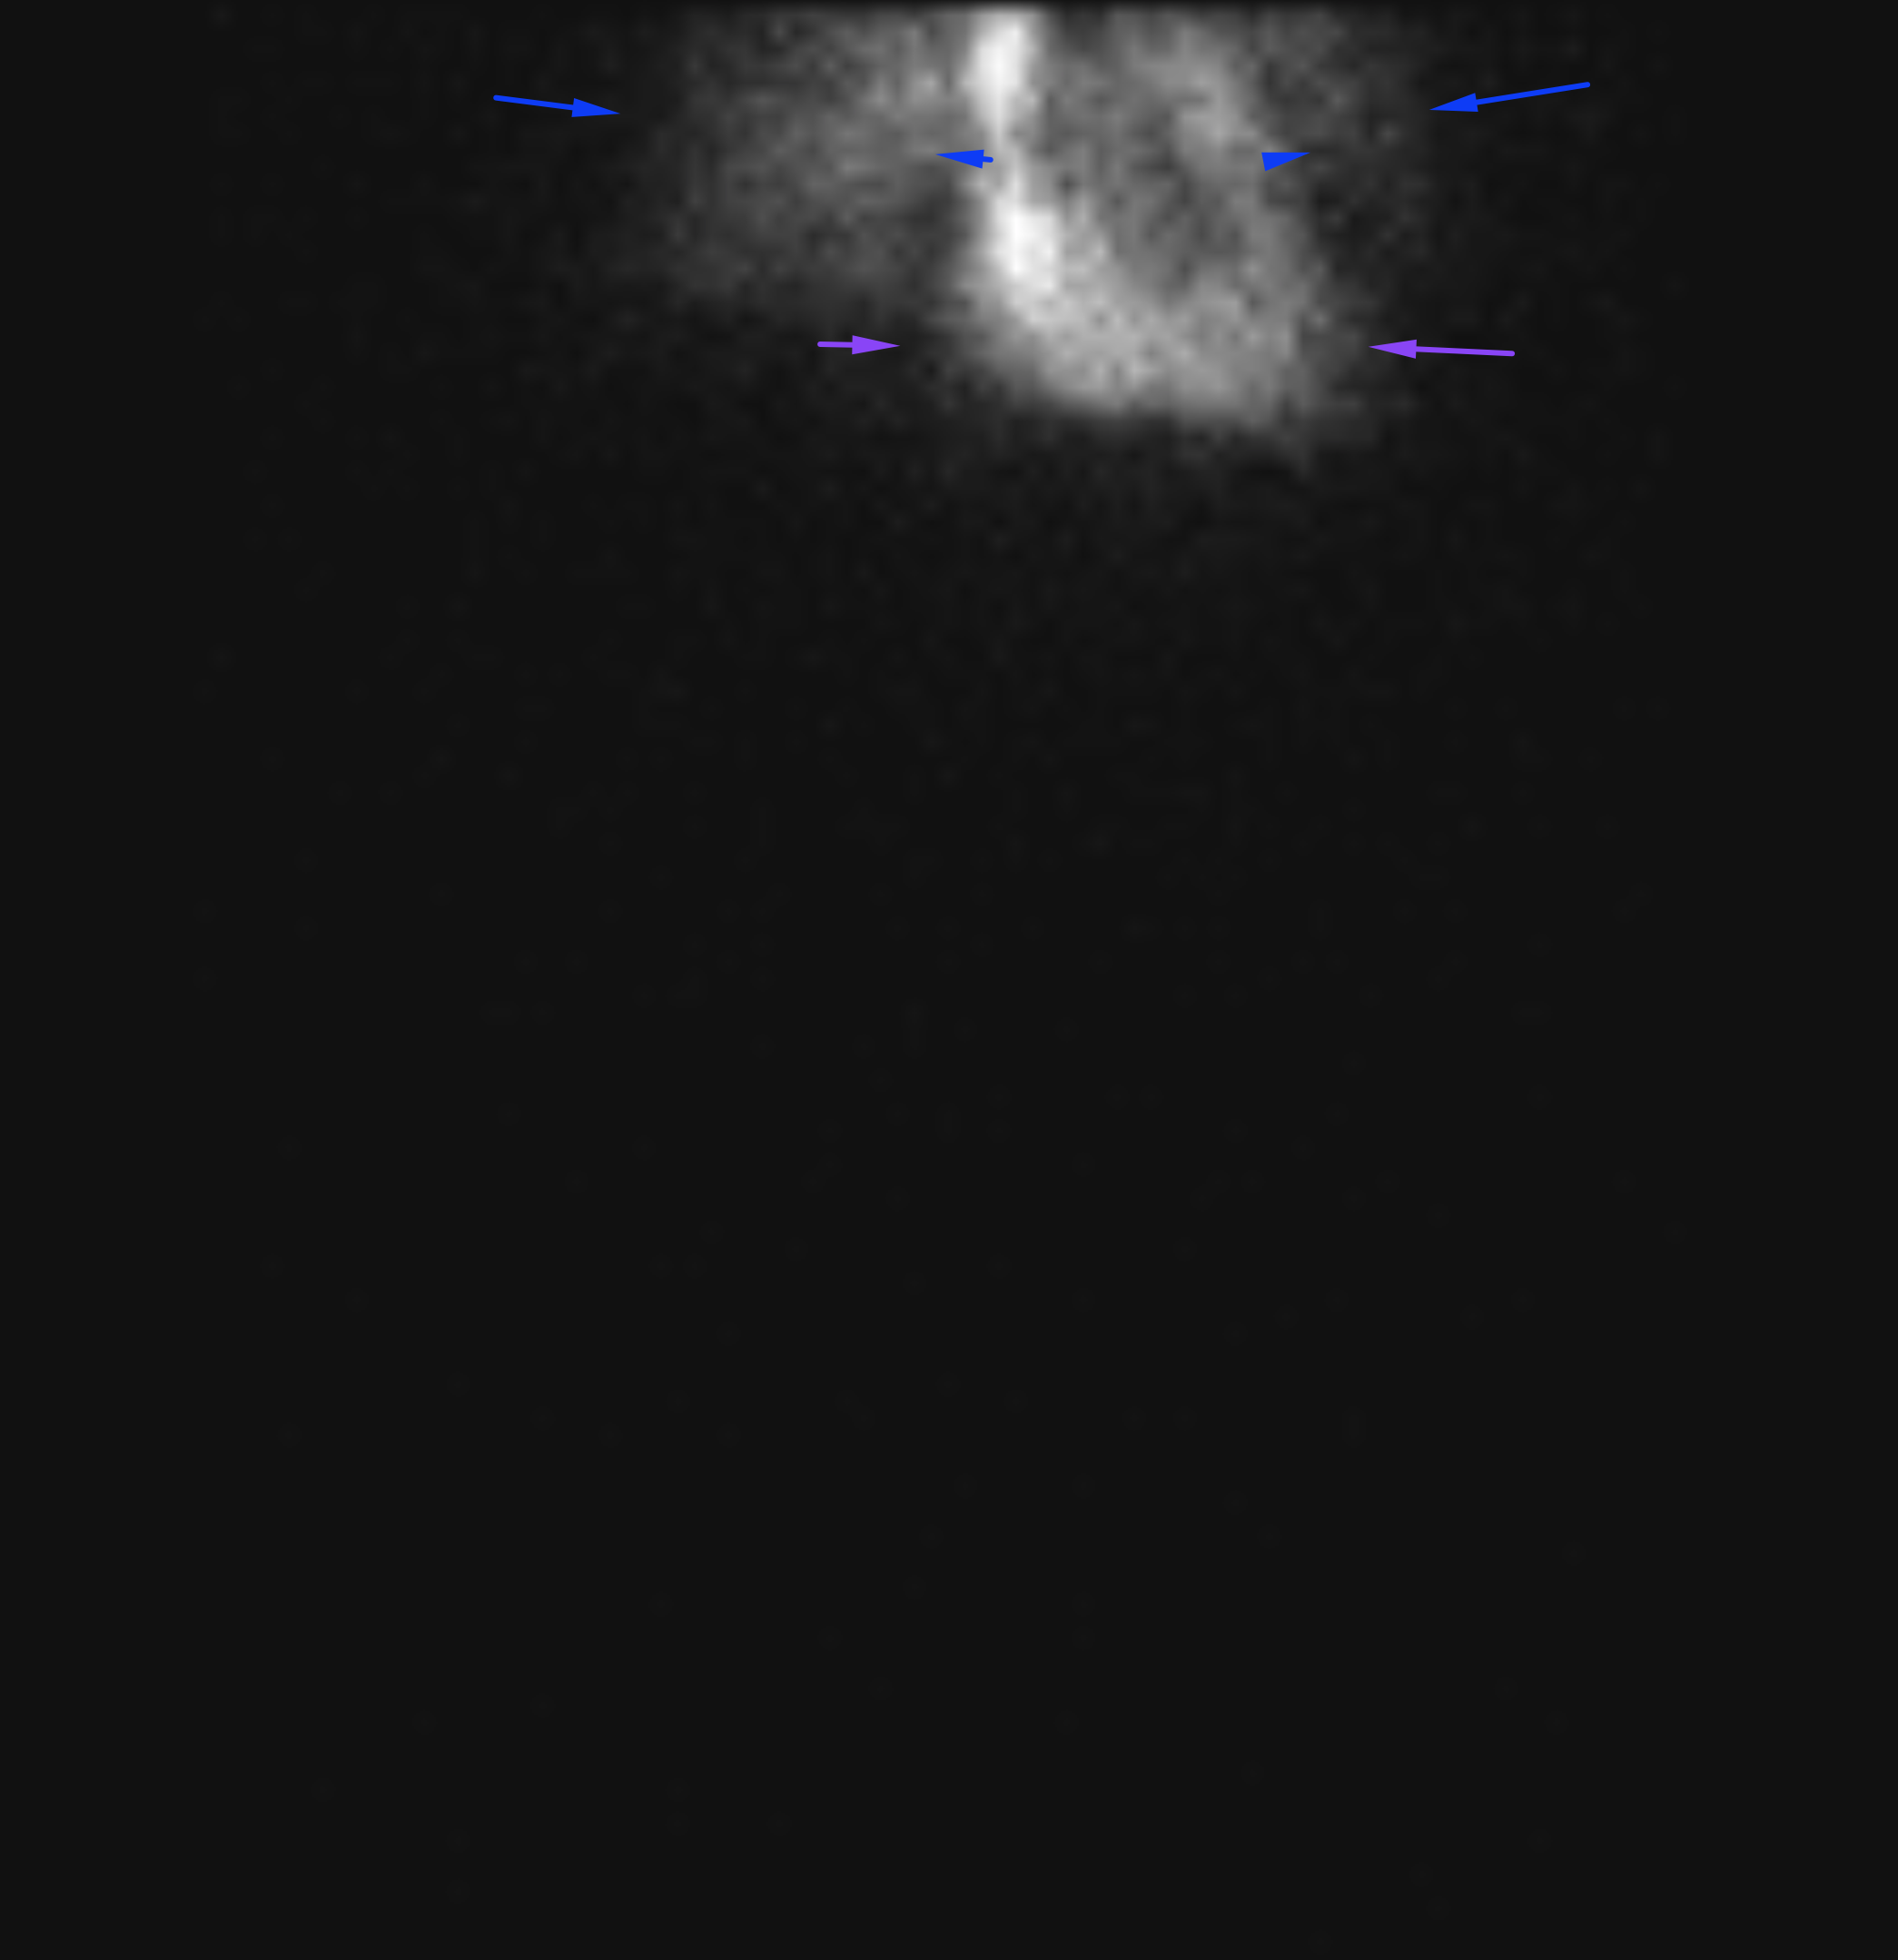

Age: 84

Sex: Female

Indication: Hematochezia with recent negative upper endoscopy and colonoscopy

Radiotracer: Tc99m labeled RBCs

Sample ReportPositive for active GI bleeding, likely originating within small bowel in the left lower quadrant.